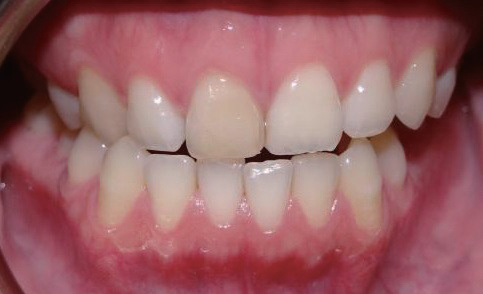

影像学检查   X线片显示11根尖尚未闭合(或根尖已经吸收),且根管宽大,可见根尖有一约8×10 mm的放射性阴影,周边牙槽骨明显缺损。询问患者自述曾经摔倒过,11受到撞击,不记得具体细节。

诊断与治疗计划   对比11 和12(图2)以及11和21(图3),11 的牙根长度较短,其根尖已出现阴影,按正常发育,11的根管应该不会如此宽大。因而推测患者在7~8 岁时,11应该曾经受到强烈撞击,导致牙髓坏死,使得根管没有继续钙化沉积,造成如今管壁相对较为单薄、根尖仍未完全闭合的情形。因而建议可在不给予局部麻醉下进行11开髓,进一步检查根管内部牙髓组织的实际状态。同时借助显微镜辅助进行根管治疗。

图2 对照12,11 根尖未闭合,牙根发育不全,且根尖周出现放射性阴影

图3 11 根管过于宽大,管壁略显薄弱,牙根长度较短